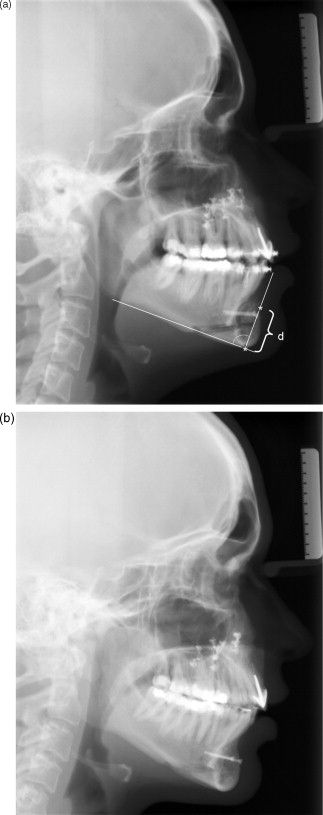

"The osteotomy presented achieves this by creating a 'chin shield' where the mandibular segment advanced is relatively high on the side of the buccal cortex and lower on the lingual side and where the osteotomy or down-fracture in between is in an oblique angle in the sagittal plane. "

"The ratio of soft tissue response to bony movement in the sliding genioplasty technique was 1:0.83, whereas in the chin shield genioplasty technique, it was 1:0.99. Conclusions: In the chin shield genioplasty technique, the increase in labiomental fold depth was less than in the sliding genioplasty technique. "

"Chin shield osteotomy technique for genioplasty is a good option for horizontal as well as vertical lengthening of chin and does not cause deepening of the mentolabial fold. "